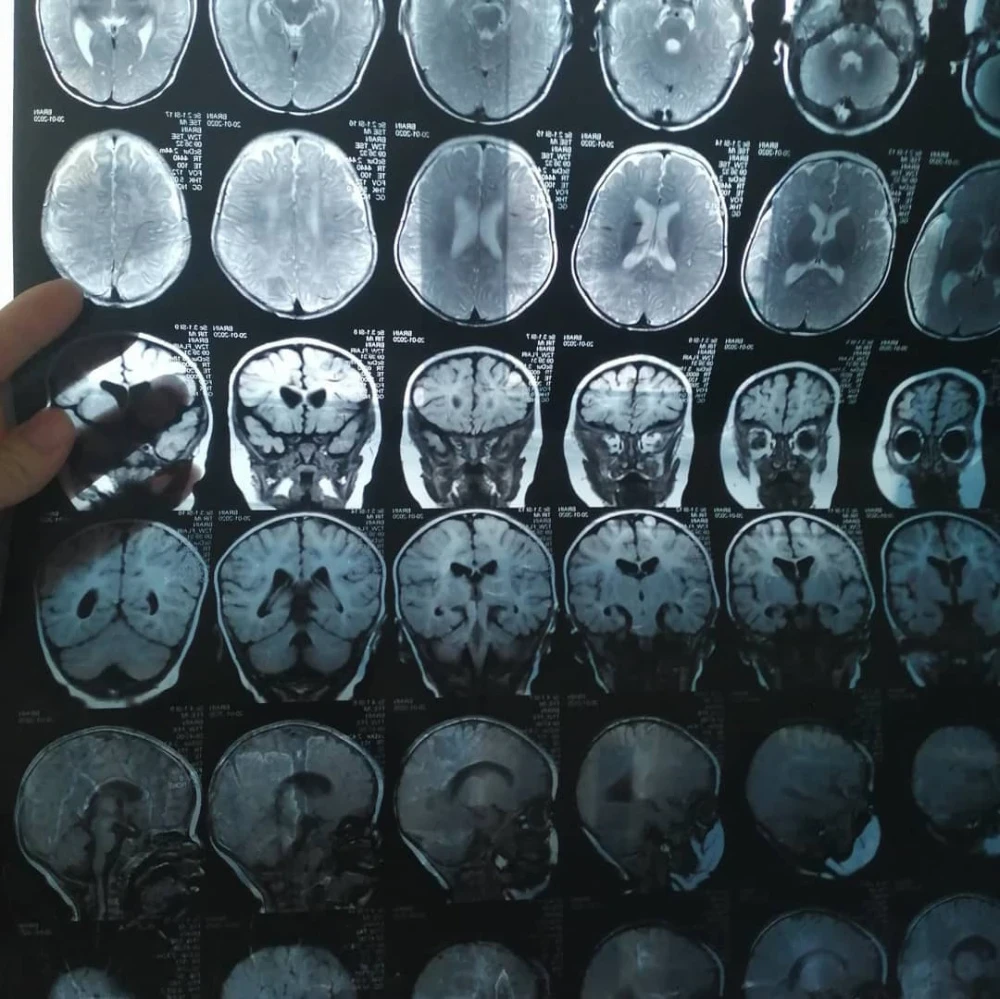

Бегимай Токтосунова стала матерью-одиночкой после развода, оставшись с дочерью, страдающей от тяжелой формы ДЦП, и больной матерью. Почти шесть лет женщина изо всех сил старается обеспечить семью, однако её дохода хватает только на повседневные нужды и поддерживающие препараты для дочери и мамы. У девочки также диагностированы сходящееся косоглазие и двусторонняя деформация голеностопного сустава, наряду с рядом других заболеваний.

Айкол уже перенесла две операции в Бишкеке, направленные на исправление двусторонней деформации голеностопного сустава, но, к сожалению, результаты оказались неудовлетворительными.